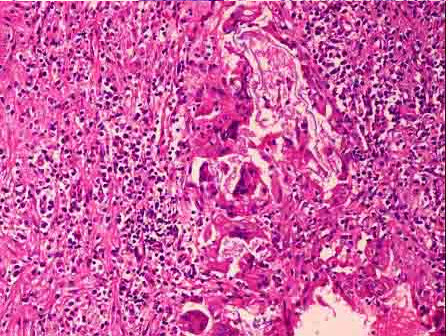

4、单项选择题

患儿,6岁,臀部皮下肌肉注射青霉素类药物4天,之后注射部位出现肿物,2周后仍未消失。

切除肿块镜检如图所示,发生了何种病变()

A.肉芽组织形成

B.异物肉芽肿形成

C.结核结节形成

D.嗜酸性肉芽肿形成

E.以上都不是

B.血管活性胺

病灶内包含的成分较多,但除外()

A.单核巨噬细胞

B.异物巨细胞

C.淋巴细胞

D.纤维母细胞

E.Langhans巨细胞